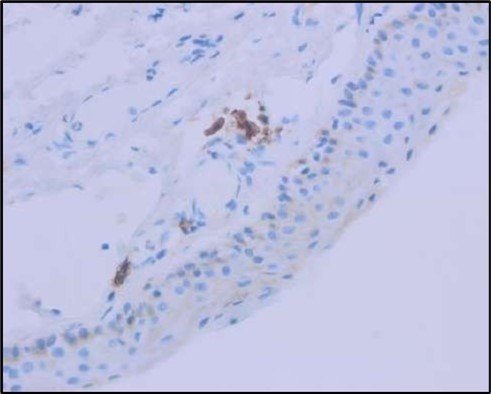

Figure 5c.OS, Immunohistochemical stain using CD45 (leukocyte common antigen) demonstrating a dense population of lymphocytes stained brown

Figure 5d.OS, Immunohistochemistry using CD138 showing many plasma cells (brown-stained) in the inflamed tissue.

Histopathological examination revealed a dense infiltration of CD138-positive plasma cells within the excised conjunctival tissue (Figure 5b, Figure 5c, Figure 5d). This finding supports an antibody-mediated immunopathogenesis in Mooren’s ulcer, consistent with Type II and Type III hypersensitivity mechanisms described in the literature 20, 21. The prominent presence of CD138- positive plasma cells provide a clear pathological rationale for conjunctival resection, as excision of the immunologically active perilimbal conjunctiva effectively removes the local 'factory' of autoantibodies that drive corneal stromal destruction, thereby halting ongoing tissue damage 21.